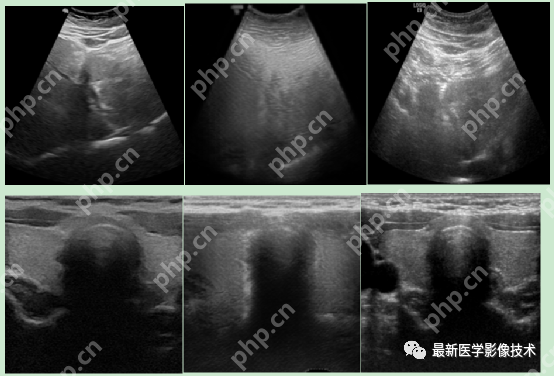

5、验证集部分生成结果

左图为低质量图像,中间为生成的高质量图像,右图为真实的高质量图像。